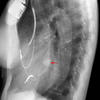

paraspinal lines

Date: 10/23/2010

Views: 3554